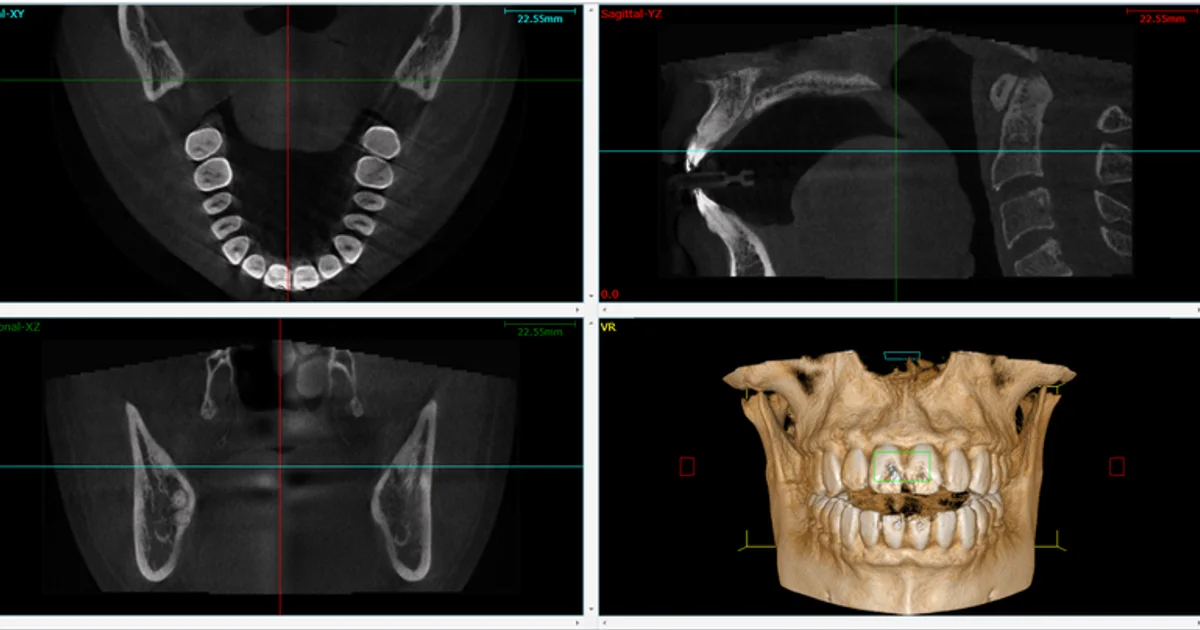

How Modern Dental Technology Enhances Preventive Care

Today’s dental technology has made preventive care faster, safer, and more effective. From digital X-rays that expose you to less radiation to intraoral cameras that let you see what the dentist sees, modern tools help build trust and improve outcomes.

Many dental offices now offer:

3D scanners instead of traditional impressions

Laser dentistry for painless gum treatment

Automated appointment reminders and digital forms to make scheduling and check-in more convenient

This investment in technology is another layer of protection that makes your preventive visits smoother and more impactful.